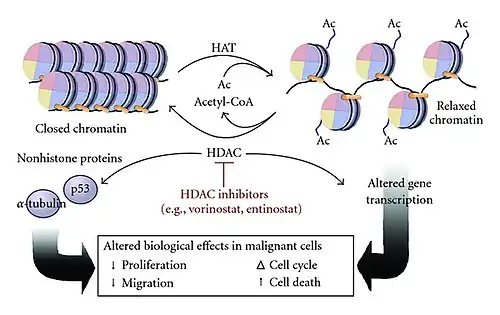

Role of HDAC Inhibitors in Promoting Neurogenesis

Histone deacetylase inhibitors (HDACi)—such as valproic acid (VPA) and trichostatin A—can enhance adult neurogenesis by blocking HDAC activity, which promotes the differentiation of adult neural progenitor cells.[19] In neural stem cells, HDAC1 and HDAC2 work with the transcription factor TLX to suppress genes that limit cell proliferation, including the cell cycle inhibitor P21 and the tumor suppressor Pten.[20] This repression supports the self-renewal and proliferation of neural stem cells. However, when HDACs are inhibited—such as by VPA, an antiepileptic drug—it can shift neural stem cells toward neuronal differentiation. Similar to processes seen in embryonic neurogenesis, VPA can also suppresses glial cell differentiation in adult neural stem cells. This effect is likely driven by the upregulation of neuron-specific genes, including neurogenic basic helix-loop-helix (bHLH) transcription factors like NEUROD, NEUROGENIN1, and MATH1. While HDAC inhibition can promote neurogenesis, complete loss of HDAC1 and HDAC2 in neural progenitor cells has the opposite effect, potentially preventing proper neuronal differentiation. Similarly, their loss in oligodendrocyte progenitor cells disrupts oligodendrocyte formation, highlighting that histone deacetylation plays distinct and essential roles at various stages of neural development.

Histone acetylation has received increasing support over the years as a proposed mechanism through which epigenetic dysregulation leads changes in gene expression that contribute to HD.[44] Studies that look at mice with HD versus the wild type (WT) have shown that specific gene loci (Drd2, Penk1, Actb, and Grin1) decrease in histone acetylation levels, suggesting that a mutation of the Huntington (HTT) gene and its overexpression may be the cause of this epigenetic dysregulation. Additionally, research has demonstrated that mutant HTT can interfere with histone acetyltransferase (HAT) activity, further reducing histone acetylation and leading to widespread transcriptional repression in neurons.[32]

It has been thought that HDAC inhibitors (HDACi's) could partially reverse the low acetylation levels seen in patients with HD. Preclinical studies have been performed using various HDACi's [such as suberoxylanilide hydroxamic acid (SAHA), Trichostatin A (TSA), phenylbutyrate, and sodium butyrate (NaB)] that target HDACI and HDACII. Although these inhibitors improve some phenotypes of HD in mice, such as neuropathology and motor function, these beneficial effects do not lead towards a conclusion for the definitive need for increasing acetylation levels in HD patients. Recent findings suggest that HDAC inhibition may not only affect histone proteins but also modulate non-histone targets involved in neuronal survival, axonal transport, and protein aggregation.[34]

However, inactivation of a target of SAHA, Hdac 4, alleviates neurodegenerative complications in mice with HD through a transcription-independent mechanism which acts upon mutant Htt aggregation processes-which may indicate that there is a mechanism involving non-histone proteins.[45] The proposed mechanism through which SAHA is speculated to act is through a RANBP2-mediated proteasome degradation model, where HDAC inhibition promotes enhanced clearance of misfolded mutant HTT aggregates.[39] In this mechanism, SAHA is shown to down-regulate Hdac 4 through an increase in sumoylation, which is then followed up with the activation of degradation through a proteasomal pathway. This mechanism reveals the connectivity between acetylation, deacetylation, and sumoylation processes.[46]

As of 2014, HDACi treatment has not been shown to restore normal expression of neuronal-identity genes.[47] However clinical studies using HDACi are currently ongoing and the results are pending, with the Phase II studies showing promise for safe and tolerable use of several compounds such as phenylbutyrate. Newer approaches are investigating more selective HDAC inhibitors that target specific isoforms, aiming to minimize off-target effects while maximizing therapeutic benefits.[34]

Given the growing evidence of epigenetic involvement in neurological and psychiatric disorders, researchers are investigating epigenetic-based therapies. HDAC inhibitors, such as valproic acid and vorinostat, have been explored as potential treatments for Alzheimer's, Parkinson's, and Huntington's diseases due to their ability to enhance gene expression related to neuronal survival and synaptic plasticity.[34]